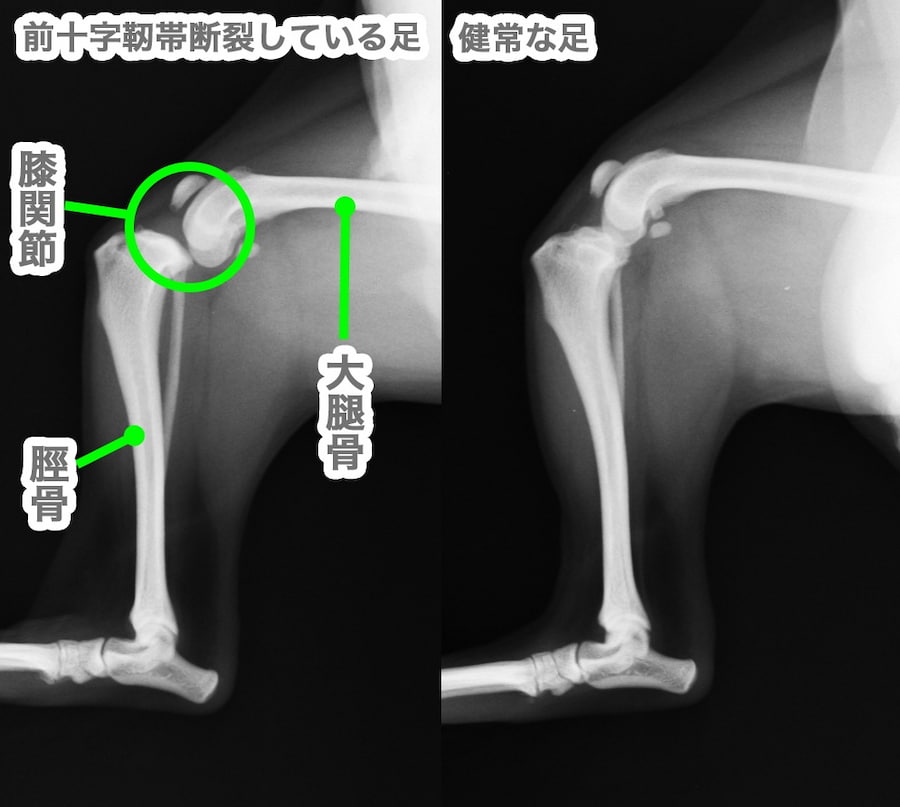

カッターで裁断したものなので、綺麗な裁断ではありません。問題なくスキャンできました。インターズー エデュワードプレス犬の前十字靱帯学治療を極めるための40章編者 PETER MUIR 監訳 泉澤 康晴310項定価 27500円(税込み)Ⅰ部 形態と機能1 十字靭帯の形態と機能2 十字靭帯の生体力学3 十字靭帯のリモデリングと修復4 半月の構造と機能5 正常およびCrCL欠損膝関節の生体力学Ⅱ部 十字靭帯断裂の疾病原因論6 前十字靭帯断裂の組織学7 前十字靭帯損傷の遺伝学8 十字靱帯の基質代謝と緩みの進行9 膝関節の形態学10 十字靭帯の変性における一酸化窒素合成と蛋白分解酵素活性の役割11 Ⅰ、Ⅱ型コラーゲン抗体の役割12 滑膜炎と膝関節の不安定性,どちらが先か?13 滑膜炎における滑膜の免疫応答の役割Ⅲ部 臨床的特徴14 前十字靭帯断裂の疫学15 十字靭帯断裂の既往歴および臨床症状16 前十字靭帯の部分および完全断裂17 後十字靭帯断裂18 膝関節のストレスX 線検査19 膝関節における超音波検査20 膝関節のコンピューター断層撮影法21 膝関節の磁気共鳴断層像Ⅳ部 手術による治療22 外科治療における関節鏡 vs.関節切開23 関節洗浄24 関節外安定化25 脛骨高平部水平化骨切り術26 脛骨粗面前進化術27 関節内法28 脛骨骨切り術を受けた前十字靭帯に障害のある膝関節の生体力学29 膝関節の安定化手術後の関節鏡によるフォローアップ検査30 前十字靱帯の辺縁切除31 前十字靱帯断裂と同時に発生する半月損傷の外科的治療32 半月解放術33 膝関節安定後における関節炎の進行34 膝関節安定術後に残存する跛行Ⅴ部 十字靭帯断裂を発症した犬の内科的管理35 膝関節炎の内科的治療36 前十字靭帯断裂を発症した犬におけるリハビリテーションⅥ部 将来の方向性37 飼い主に限定した結果の測定38 犬の人工膝関節全置換術39 再生医療と前十字靱帯の修復40 疾患修飾療法書き込み等確認しておりますが確認漏れや、一度人の手に渡った商品であることをご理解の上でご購入よろしくお願いいたします。匿名配送獣医臨床小動物動物病院動物看護ペット